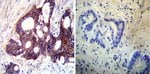

MA3-928 detects sodium/potassium ATPase alpha from human, mouse, bovine, sheep, canine, chicken and porcine tissues. This antibody detects the alpha 3 isoform in rat only. MA3-928 has been successfully used in Western blot, immunohistochemistry, immunoprecipitation, immunocytochemistry, immunofluorescence, and ELISA procedures. By Western blot, this antibody detects an ∽110 kDa protein representing alpha sodium/potassium ATPase from MDCK cell extract. Immunohistochemical staining of alpha sodium/potassium ATPase in porcine heart with MA3-928 yields a pattern consistent with the plasma membrane localization. The MA3-928 antigen is purified sheep kidney alpha sodium/potassium ATPase. This antibody recognizes an epitope between amino acid residues 646 and 652 of the sheep kidney alpha sodium/potassium ATPase.